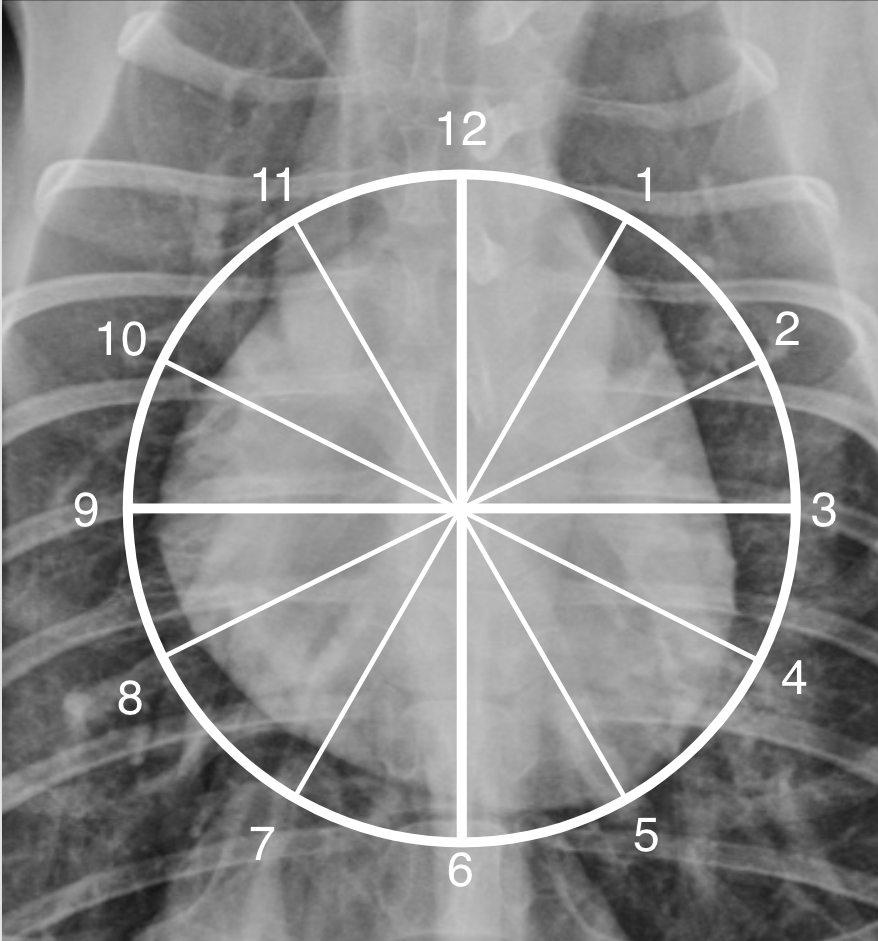

Describe the cardiovascular structures using the “clokc analogy” in DV/VD position.

A

Clock face analogy to identifying the location of the cardiac chambers

_Lateral view:_ * **12-2 o'clock:** left atrium * **2-5 o'clock:** left ventricle * **5-9 o'clock:** right ventricle * **9-10 o'clock:** main pulmonary artery and right auricular appendage * **10-11 o'clock:** aortic arch _Dorsoventral view:_ * **11-1 o'clock:** aortic arch * **1-2 o'clock:** main pulmonary artery (left auricular appendage in cat) * **2.30-3 o'clock:** left auricular appendage * **2-5 o'clock:** left ventricle * **5-9 o'clock:** right ventricle * **9-11 o'clock:** right atrium _Species differences:_ * On a VD/DV view the cardiac apex points more to the left in the dog. In the cat the apex is more variable, but usually closer to the midline. * **In the dog the left auricular appendage (LAu)** is located at **02.30-03.00 o'clock** on the **DV/VD view. In the cat the LA and LAu** are located at **1-2 o'clock** on this view and the main pulmonary artery may be cranial to this or not seen at all. * In the cat the more cranial location of the LA may make it difficult to see on the lateral view. * **In the dog, when the LA is enlarged** on the **DV/VD view** is superimposed over the cardiac silhouette in the **5-7 o'clock position** (between the caudal mainstem bronchi), whereas in the **cat, it is located more cranially at the 1-2 o'clock position**. This explains the so-called 'valentine heart shape' seen only in the cat and created by left ± right atrial enlargement.